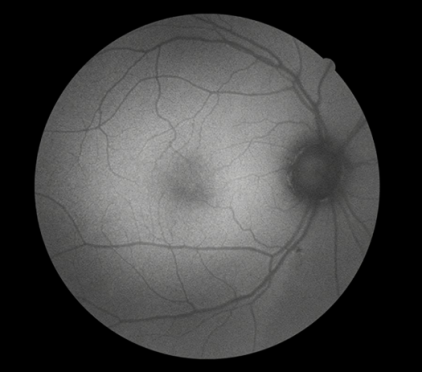

FFA是20世纪60年代发展的一项技术。1961年Navotny 和Alvis首次成功地用胶片记录到荧光素流经视网膜和脉络膜血管的动态过程,开创了眼底荧光血管造影的临床应用时代。如今,FFA主要用于观察视网膜血管及其血液循环状态,高清晰摄像技术能动态捕捉视网膜毛细血管的循环状态,间断或连续采集可形成视网膜静态的黑白图像或动态图像,在诊断中敏感性强,确诊率高,能发现检眼镜或眼底照相下不易发现的视网膜深层微血管瘤,是判断视网膜病变的“金标准”。

FFA影像